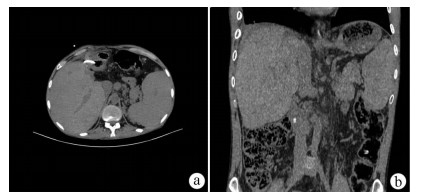

Jaundice and portal hypertension caused by hepatic epithelioid hemangioendothelioma: A case report

Ruihua ZHANG, Tingting QIN, Yueming SHAO, Yu ZHANG, Yang WANG, Xiaoyu WEN

2021, 37(7): 1662-1664. DOI: 10.3969/j.issn.1001-5256.2021.07.036

Abstract(1181) HTML (235) PDF (2873KB)(100)

Abstract: